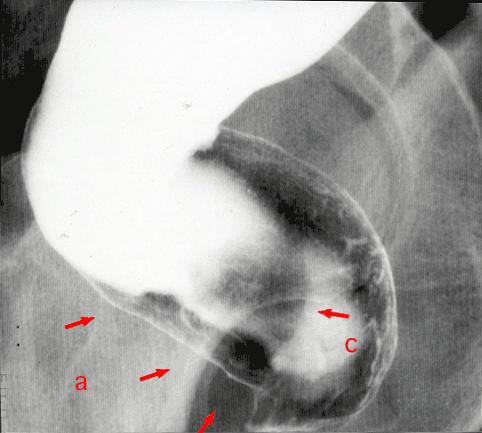

疾病(病理主体)的分类恶性非上皮性肿瘤/平滑肌肉瘤

部位(按器官分)大肠/直肠

检查方法X线

肿瘤最大直径40以上

肿瘤的深度ss(a1)